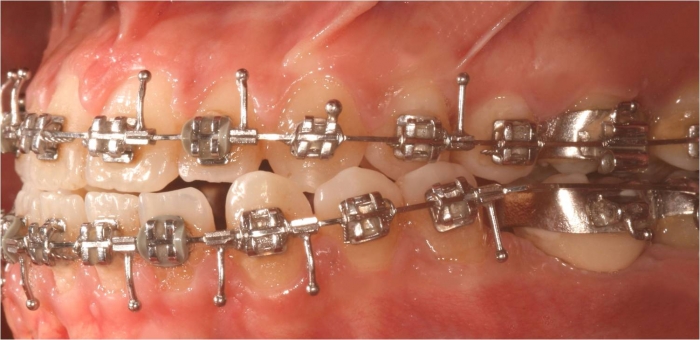

Mordida inicial

Mordida final